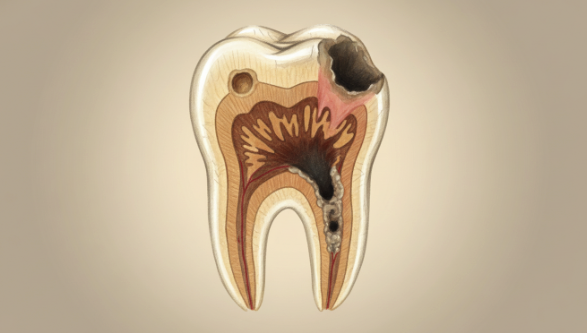

虫歯の進行段階と治療法

虫歯は、進行度によって治療方法が変わります。

ここでは、進行度別の虫歯の治療方法と流れを解説します。虫歯の進行段階は、C0からC4までの5段階に分類されます。

C0(初期虫歯)

初期虫歯とは、歯の表面のエナメル質がすこしずつ溶け始めている状態で、健康な歯よりも歯にツヤがなくなった状態です。この状態の場合、歯を削るなどの大きな処置は行われず、歯磨きや歯医者での定期健診での治療が可能です。

C1(エナメル質の虫歯)

エナメル質の虫歯は、エナメル質が溶けて、歯の表面に小さな穴が空いた状態です。この状態の虫歯の治療では、歯を削り、コンポジットレジンと呼ばれる白いプラスチックを詰める処置がされます。歯を削る量がすくないため、1回の治療で終えることができます。

C2(象牙質の虫歯)

象牙質の虫歯は、虫歯が歯の内部まで広がって象牙質まで進行した状態で、冷たいものを口にすると痛みが生じるなどの症状があります。この状態の虫歯では、虫歯の部分を削り、詰め物をする処置がされます。詰め物を作るため、通院回数は最低でも2回、約1週間ほどの時間が必要です。

C3(神経まで進行した虫歯)

虫歯が神経まで進行していると、歯に大きな穴が開いており、激しい痛みを生じます。この状態の場合、神経を抜き、歯を削って土台を作って被せ物をします。治療には、被せ物を作るため、約1ヶ月の期間が必要です。

C4(歯根まで進行した虫歯)

虫歯が歯根まで進行していると、歯の見える部分が見えなくなり、場合によっては、歯の神経が死んでしまい、痛みを感じなくなることもあります。この状態の場合では、歯を抜かなければならないことが多いです。そのため、歯を抜いて、ブリッジや入れ歯、または、保険適用外ではありますがインプラントによって抜いた歯の機能を補います。